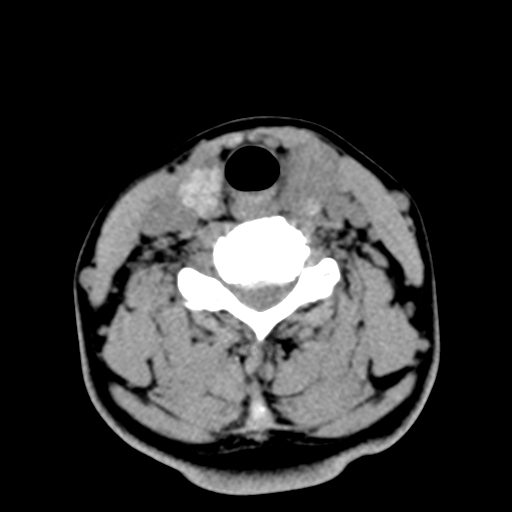

女,44岁,左颈部肿块伴疼痛两个月。患者不能做增强扫描。

左侧甲状腺明显肿大,密度不均匀性减低,正常之钙化基本消失,残留少许呈云雾状及颗粒状。其边缘不规则、不清晰,与前部联合处正常甲状腺不能分界不清,但尚可与周围其他组织分辨。颈动脉鞘区无明显淋巴结肿大。

多考虑:左侧甲状腺癌。

多考虑:左侧甲状腺占位,建议穿刺活检。